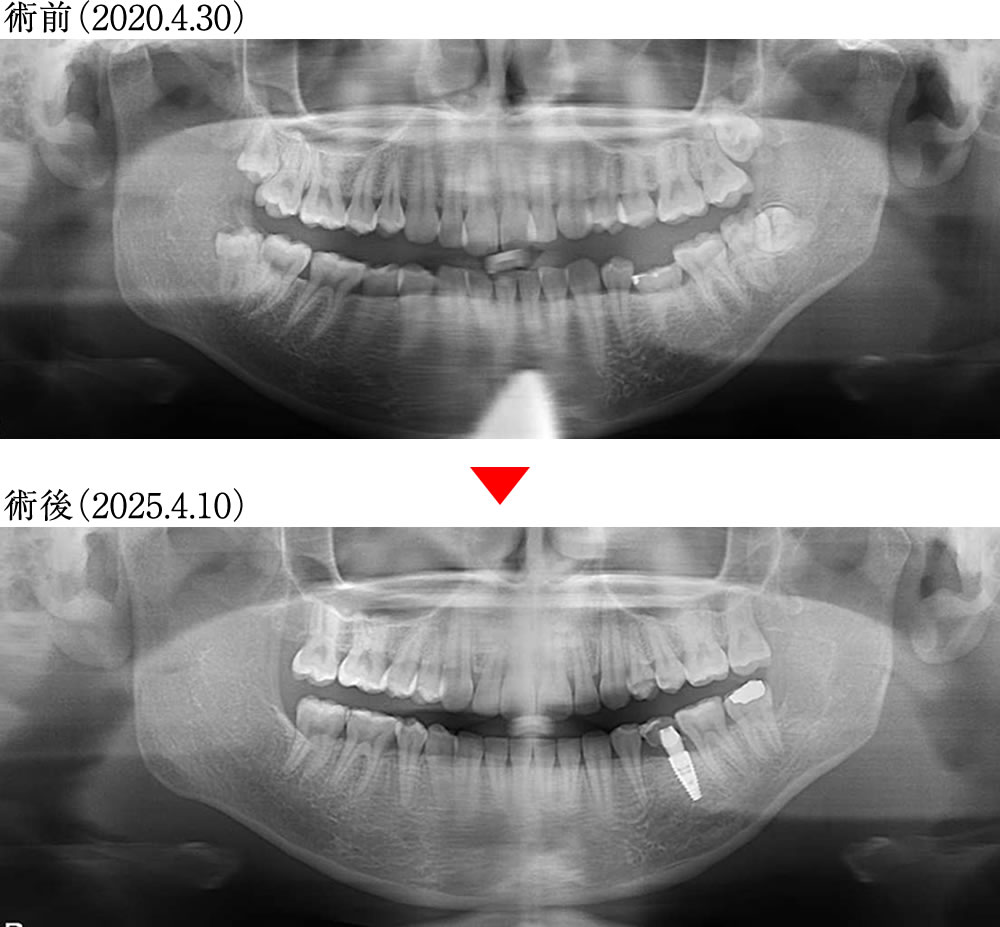

治療前後のレントゲン画像

治療前は親知らず、乳臼歯の残存で不確定要素が混在した口腔でした。治療後は不確定要素がなくなり整った歯軸でFLATな咬合平面という理想的な環境になりました。